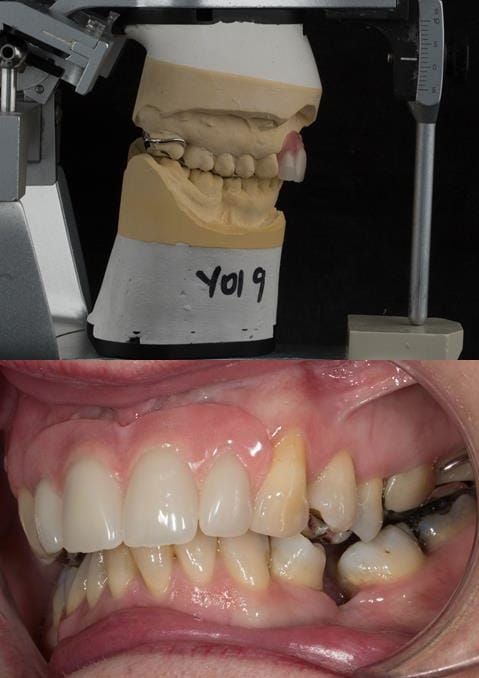

Provision of a maxillary cobalt chromium based partial denture/protective occlusal splint in a heavily restored dentition

Following consultation and second discussion appointment the patient chose to have option 3 namely, a maxillary cobalt chromium based partial denture/protective occlusal splint. The clinical situation and treatment process is shown in detail below with photographs. The patient was successfully rehabilitated with this and her quality of life considerably improved. The clinical work was provided by Finlay and the technical work by Rowan.